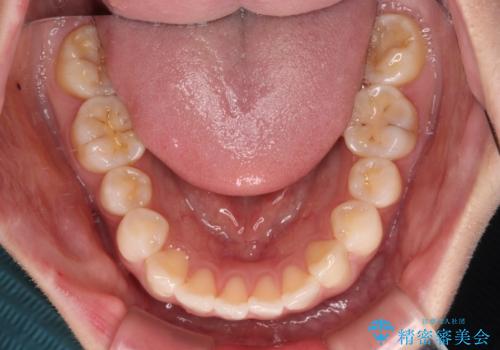

- 前歯のデコボコと、上下前歯が接触せずに前に飛び出していることを気にして来院された患者様です。

舌の突出癖が強く、それが原因で上顎歯列全体が前方に突出し、上下前歯が接触できない状態となっていました。

補助装置を用いて上顎臼歯を後方移動させ、歯列を整えながら前歯部の接触を図ることとしました。